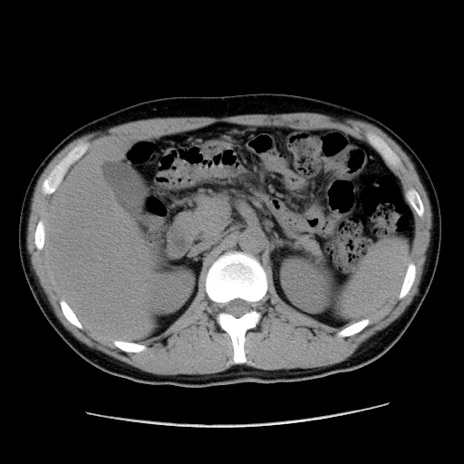

冠状断像

【症例】20歳代 男性

【主訴】心窩部痛

【現病歴】今朝より上腹部痛あり。一旦軽快していたが再度出現したため救急要請。昨日夕に白身の魚を含む刺身を食べた。

【身体所見】BP 136/89mmHg、HR 74/min、BT 37.0℃、腹部:膨満、軟、心窩部に圧痛あり。反跳痛なし、筋性防御なし、腸雑音やや亢進あり。

【データ】WBC 17700、CRP 0.48